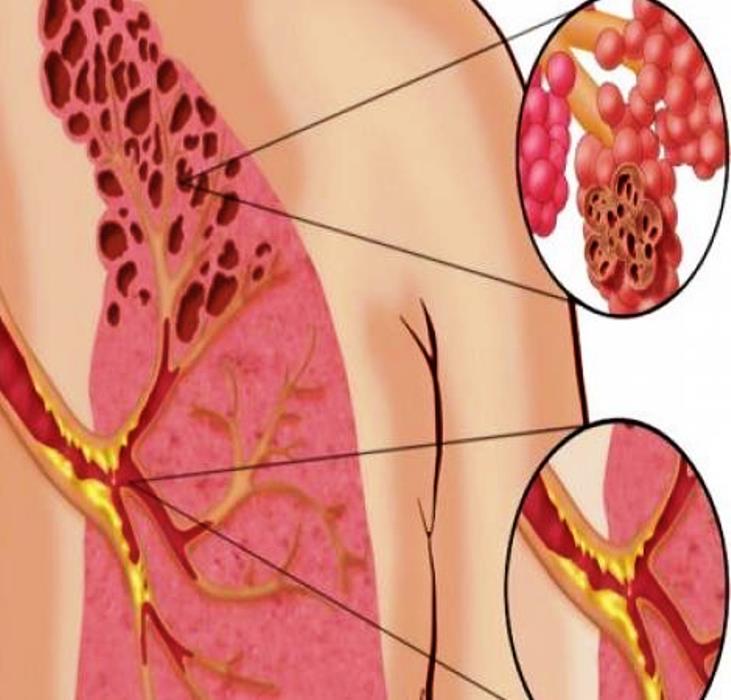

Even though the underlying cause of the illness has not been identified, all cases involve vaping and many involve vaping THC or tetrahydrocannabinol, a psychoactive constituent of cannabis.

“Vaping exposes users to many different substances for which we have little information about related harms – including flavourings, nicotine, cannabinoids and solvents.”